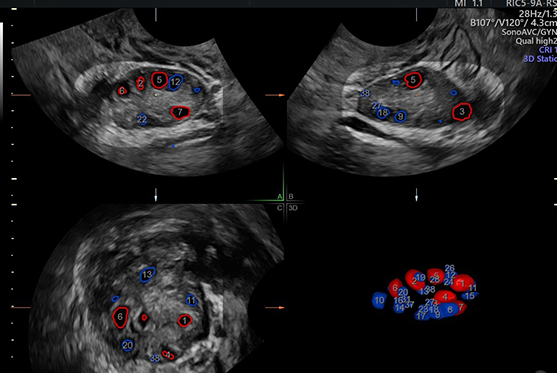

• Step 2: Ultrasound (AFC Scan) – A transvaginal ultrasound is performed to count the antral follicles in both ovaries. This scan is painless and takes about 10–15 minutes.